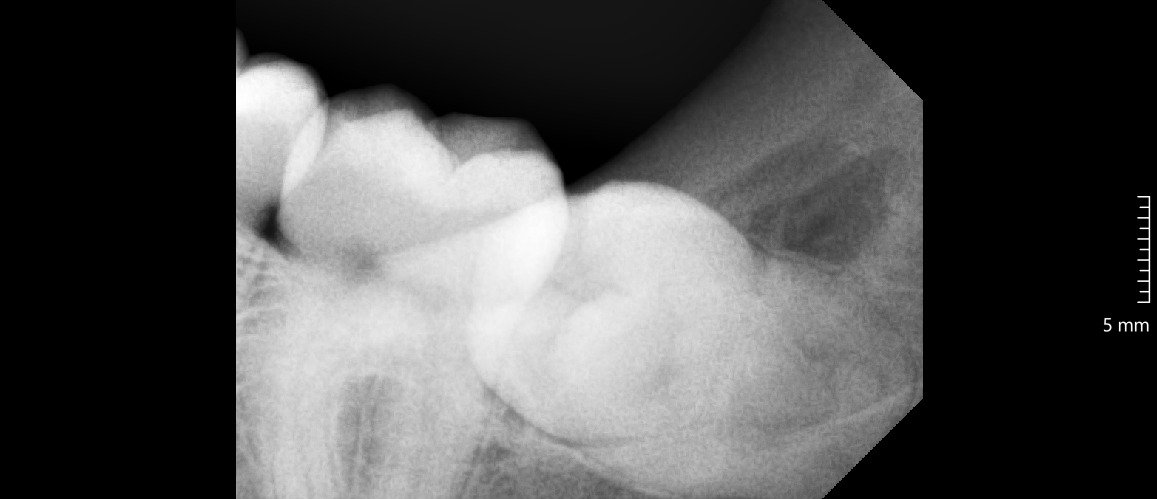

Odontektomi adalah prosedur bedah gigi untuk mengangkat gigi yang sulit dicabut dengan metode biasa. Dokter gigi biasanya melakukan tindakan ini pada gigi dengan impaksi, yaitu gigi yang tumbuh sebagian atau sepenuhnya terpendam di dalam gusi maupun tulang rahang.

Kasus paling sering yang membutuhkan odontektomi terjadi pada gigi bungsu (molar tiga). Gigi bungsu yang tumbuh miring atau kekurangan ruang di rahang sering menimbulkan nyeri, infeksi, serta gangguan pada gigi sebelahnya.